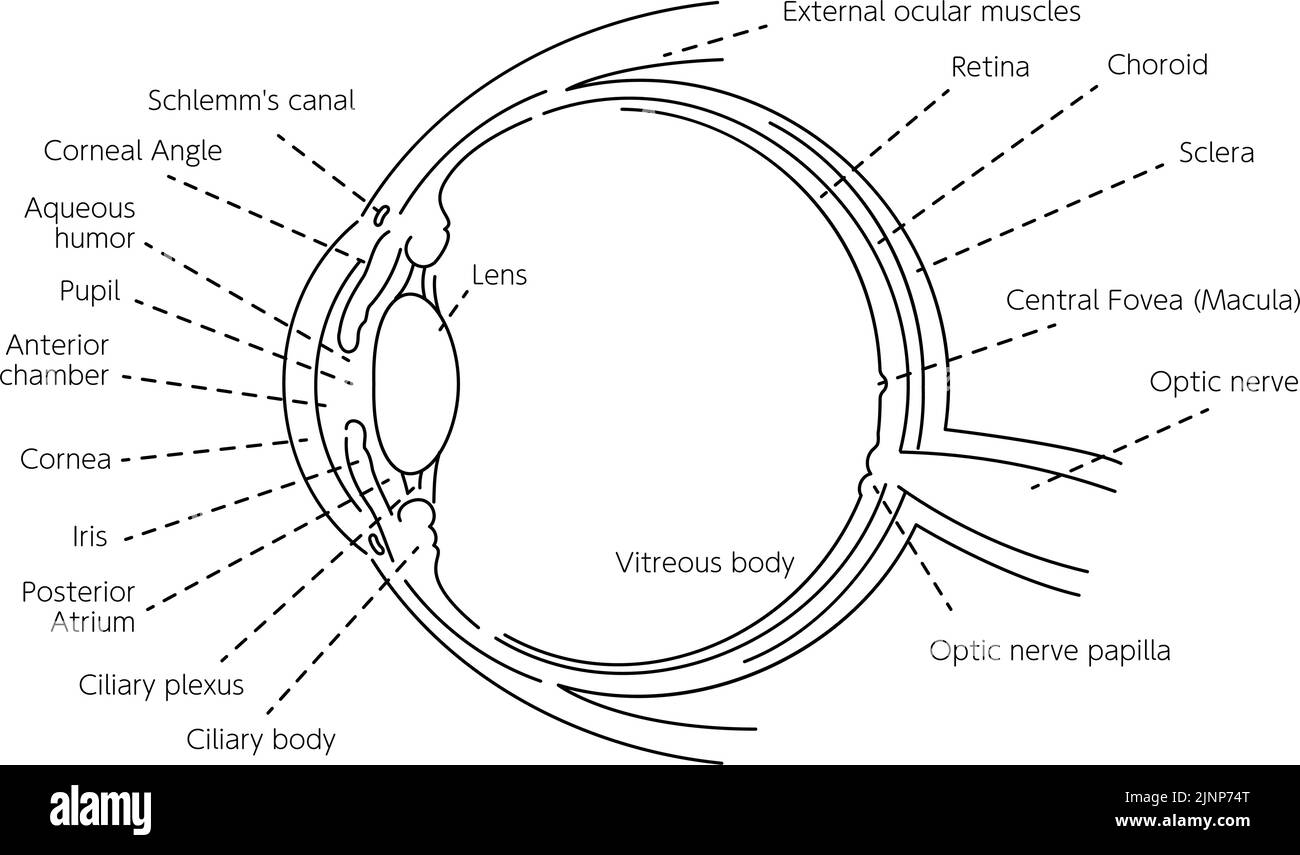

Diagrammatic illustration of the eye (line drawing) Stock Vectorhttps://www.alamy.com/image-license-details/?v=1https://www.alamy.com/diagrammatic-illustration-of-the-eye-line-drawing-image478074574.html

Diagrammatic illustration of the eye (line drawing) Stock Vectorhttps://www.alamy.com/image-license-details/?v=1https://www.alamy.com/diagrammatic-illustration-of-the-eye-line-drawing-image478074574.htmlRF2JNP4YX–Diagrammatic illustration of the eye (line drawing)

Illustration of the eye - Translation: Schlemm's canal, corner angle, aqueous humor, pupil, anterior chamber, cornea, iris, posterior chamber, ciliary Stock Vectorhttps://www.alamy.com/image-license-details/?v=1https://www.alamy.com/illustration-of-the-eye-translation-schlemms-canal-corner-angle-aqueous-humor-pupil-anterior-chamber-cornea-iris-posterior-chamber-ciliary-image478075540.html

Illustration of the eye - Translation: Schlemm's canal, corner angle, aqueous humor, pupil, anterior chamber, cornea, iris, posterior chamber, ciliary Stock Vectorhttps://www.alamy.com/image-license-details/?v=1https://www.alamy.com/illustration-of-the-eye-translation-schlemms-canal-corner-angle-aqueous-humor-pupil-anterior-chamber-cornea-iris-posterior-chamber-ciliary-image478075540.htmlRF2JNP66C–Illustration of the eye - Translation: Schlemm's canal, corner angle, aqueous humor, pupil, anterior chamber, cornea, iris, posterior chamber, ciliary